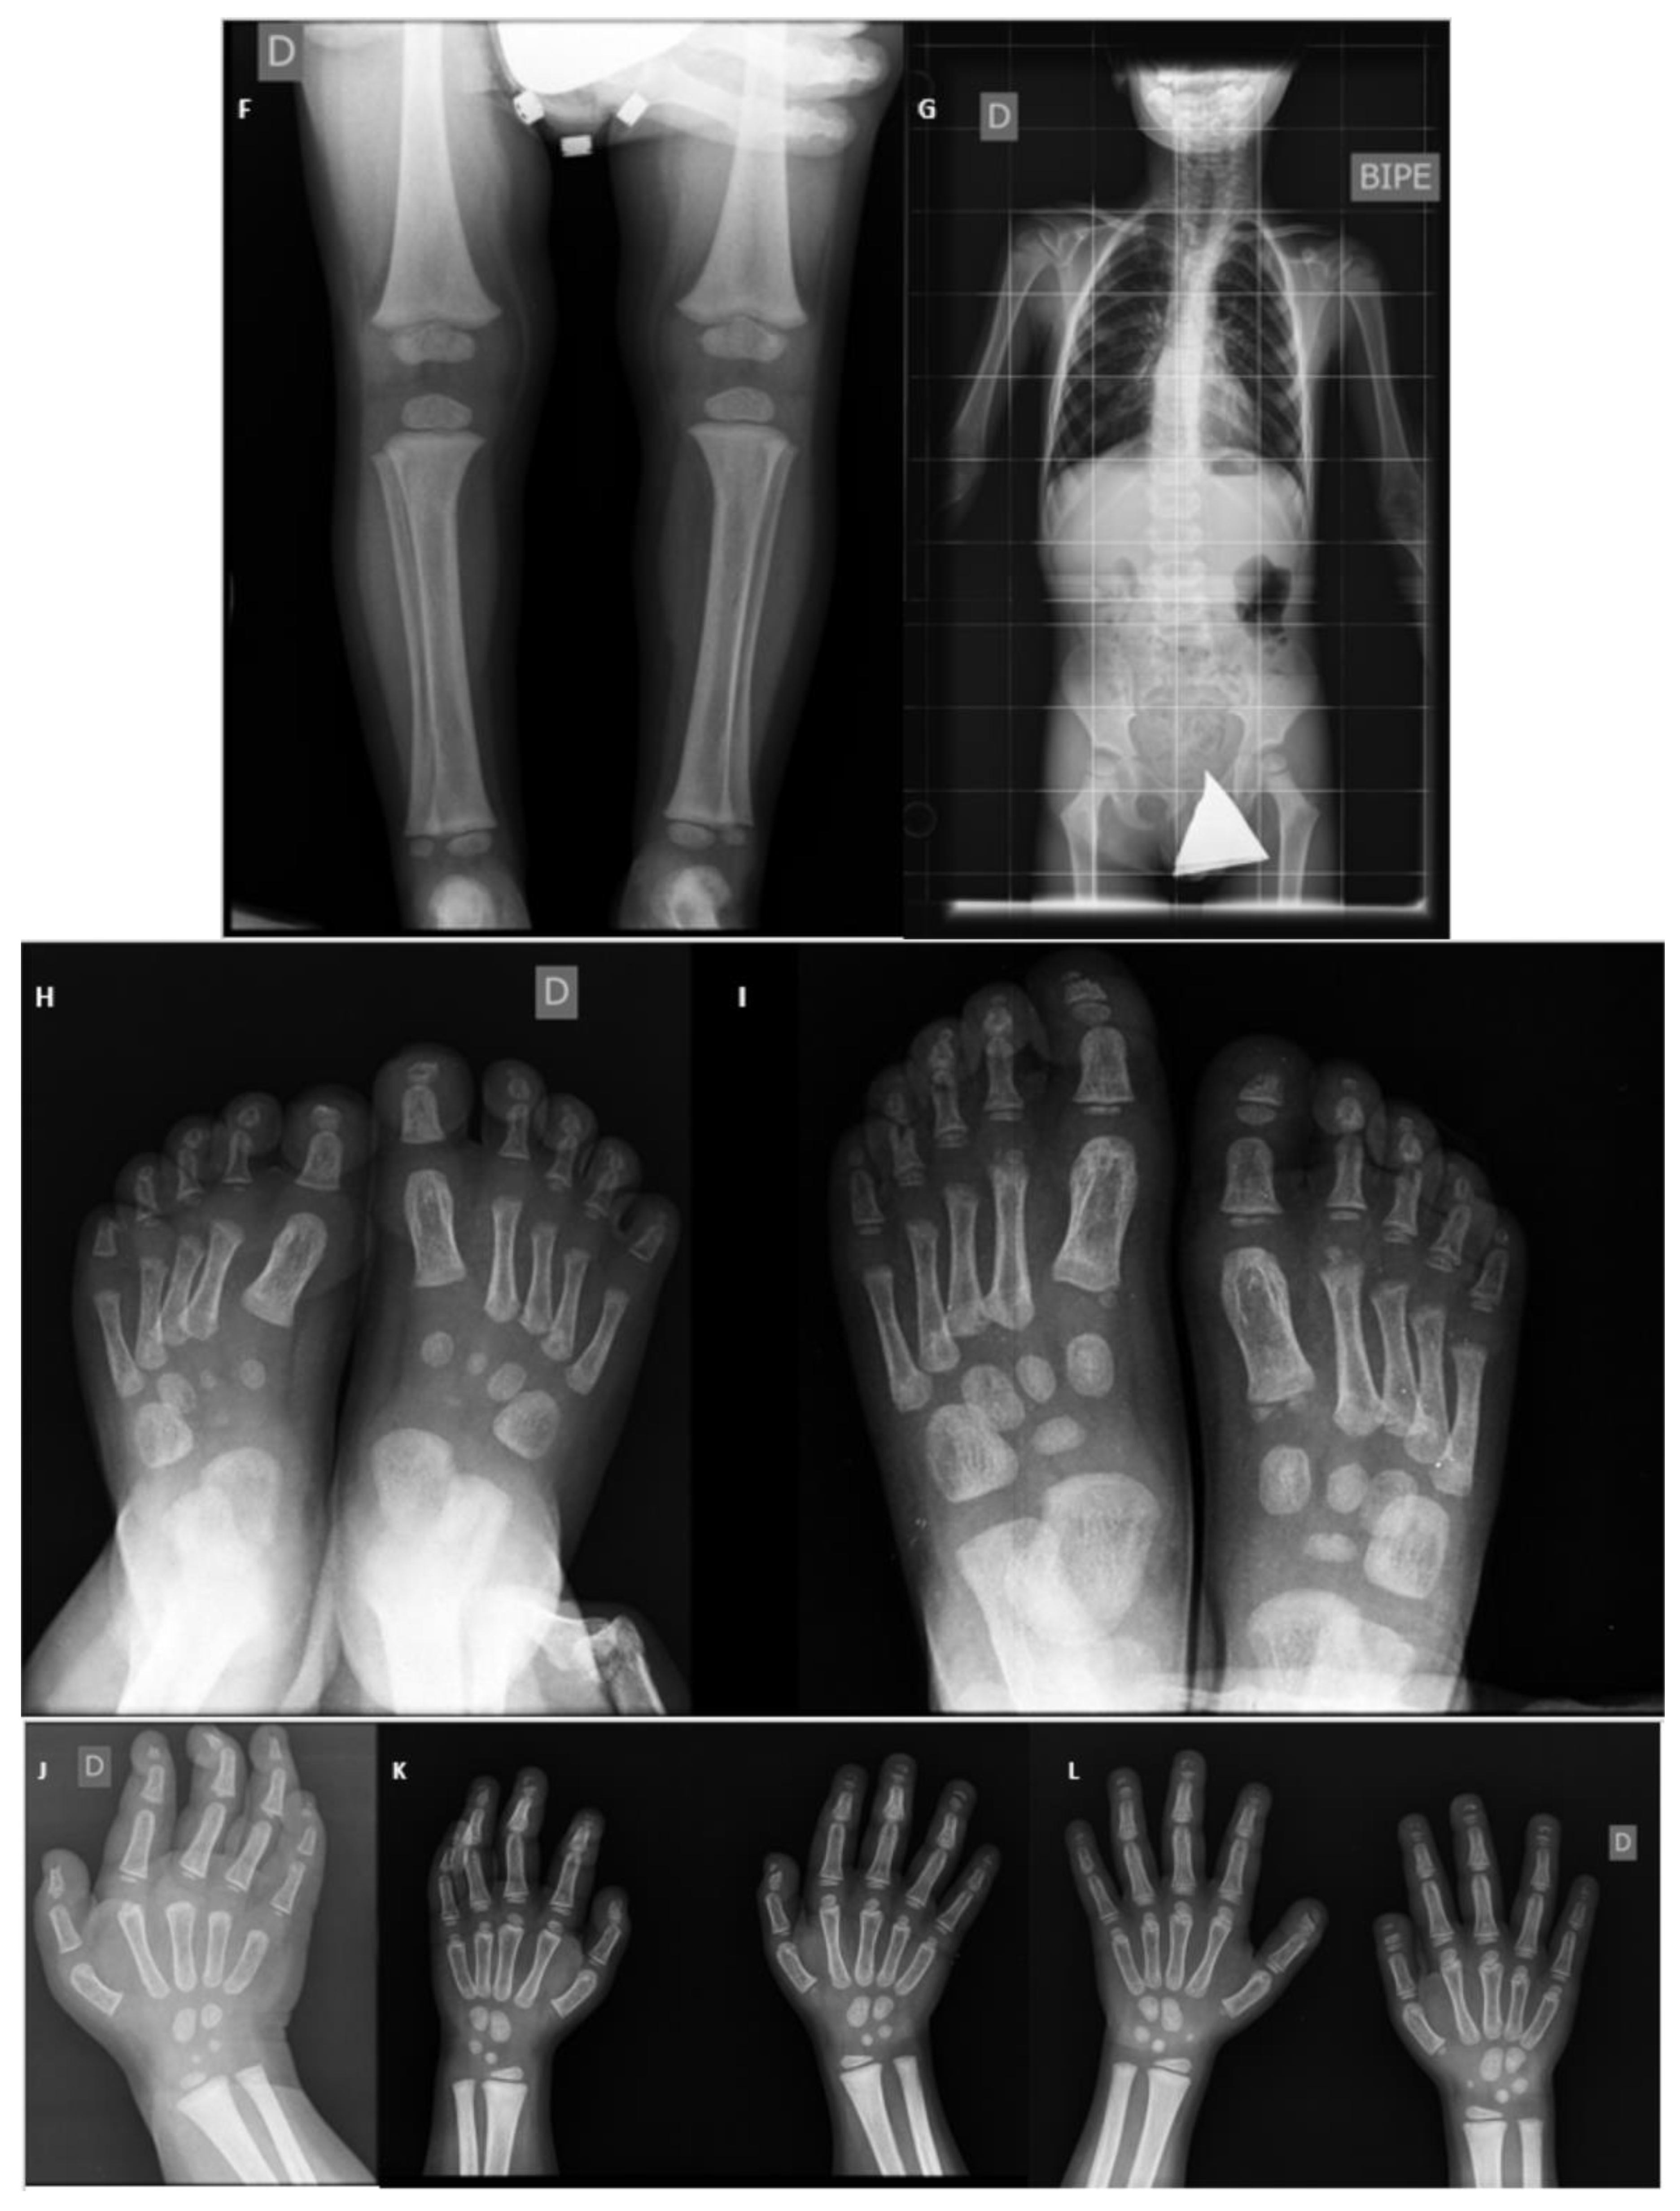

2. Patient Information

3. Musculoskeletal Features